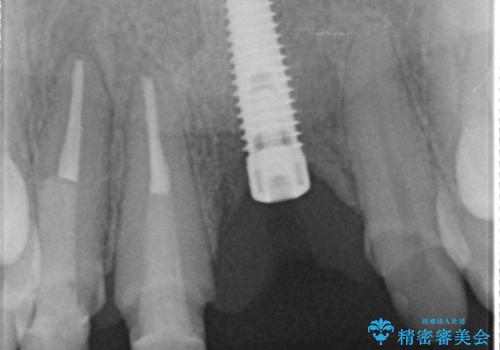

左側の前歯には他院で埋入されたポジションの悪いインプラント補綴により歯冠長の長いクラウンが装着されており、感染による排膿も認められこのまま審美性を改善するのは難しい状態です。

感染したインプラントからは排膿が間欠的に認められ、掻爬・除去が検討されうるような状況でした。